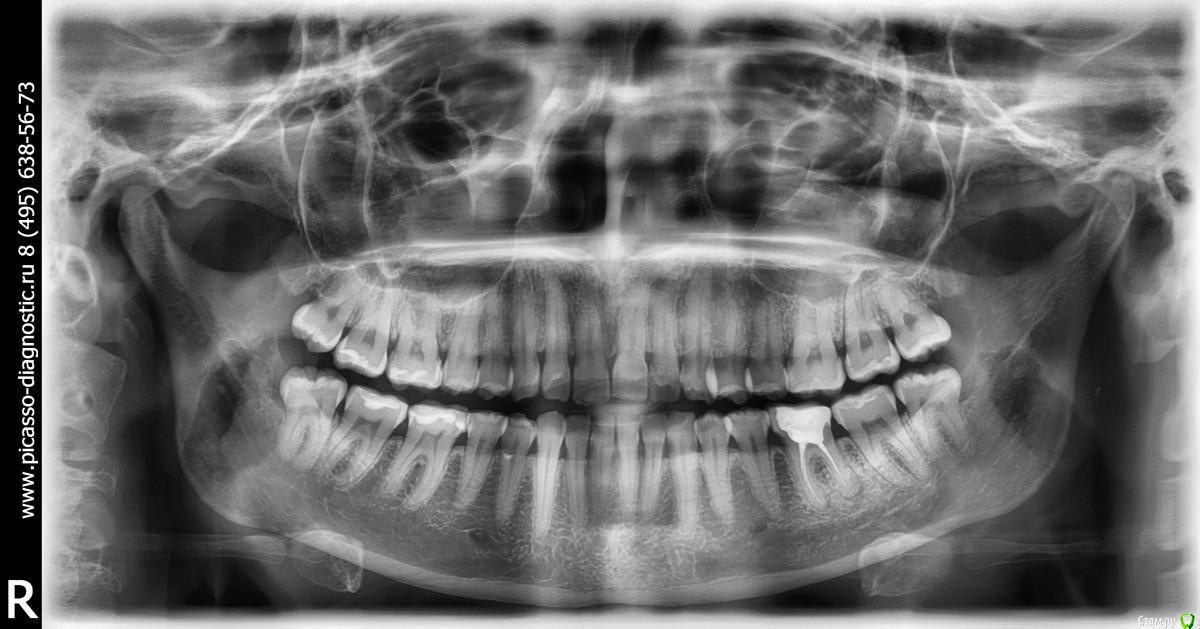

Марина4444 Опубликовано 15 августа, 2017 Поделиться Опубликовано 15 августа, 2017 (изменено) Уважаемые специалисты! посоветуйте оставлять(пломбировать) восьмерки или удалить,дискомфорта нет,но есть кариес.Заранее спасибо! Изменено 15 августа, 2017 пользователем Марина4444 Ссылка на комментарий

red_butler Опубликовано 15 августа, 2017 Поделиться Опубликовано 15 августа, 2017 А можно подробней? какие показания к удалению?не правильное положение и - есть кариес Ссылка на комментарий

IvanK Опубликовано 15 августа, 2017 Поделиться Опубликовано 15 августа, 2017 Я тоже за удаление Ссылка на комментарий